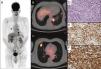

Se realizó una tomografía por emisión de positrones/axial computarizada (PET/TAC) con F18-fluorodeoxiglucosa (18F-FDG PET/TC) a un varón de 72 años con antecedentes de micosis fungoide con afectación cutánea, en remisión clínica postratamiento, para realizar de nuevo la estadificación tras la reciente detección de nódulos pulmonares en una TC. Las imágenes de PET/TC mostraron múltiples zonas de aumento del valor de captación del radiofármaco correspondientes a varios nódulos pulmonares bilaterales (fig. 1A-C).

La imagen de cuerpo entero con proyección de máxima intensidad (MIP) mediante 18F-FDG PET (A) y las imágenes axiales PET/TC fusionadas (B, C) mostraron zonas con aumento del valor de captación de 18F-FDG correspondientes a nódulos pulmonares bilaterales (flechas). El análisis histológico de uno de los nódulos pulmonares demostró la presencia de infiltración intersticial de elementos linfoides de tamaño pequeño-mediano con citoplasma claro (D). En el análisis inmunohistoquímico, las células tumorales expresaron CD3 (E) y CD4 (F). El diagnóstico definitivo fue de micosis fungoide con afectación pulmonar.

En consecuencia, se realizó la biopsia de uno de los nódulos pulmonares del paciente. El análisis histológico demostró la presencia de infiltración intersticial de elementos linfoides de tamaño pequeño-mediano con citoplasma claro. En el análisis inmunohistoquímico, las células tumorales expresaron CD3 y CD4 (fig. 1D-F).

A partir de estos hallazgos, el diagnóstico definitivo fue de micosis fungoide (MF) con afectación pulmonar y se remitió el paciente a quimioterapia.